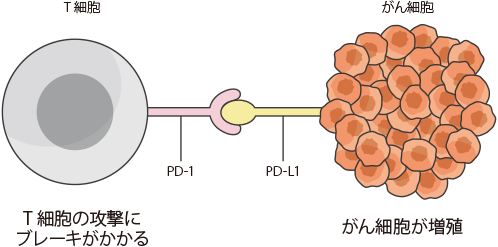

しかし、がん細胞は、免疫の攻撃から逃れるために、免疫細胞(T細胞など)にブレーキをかける力をもっています。このように、がん細胞によって免疫にブレーキがかけられた状態や、もともと免疫の働きが弱まった状態などでは、がん細胞を排除しきれないことがあります。

免疫の働きにブレーキをかける免疫チェックポイント

私たちの体には、細菌やウイルスなど外来の異物や、体の中でできたがん細胞などの異常な細胞の働きを抑えこみ、排除するための「免疫」という仕組みがあります。さらに免疫が過剰に働き、自分の体を攻撃しないように、免疫にブレーキをかける仕組みも備わっていることがわかってきました。がん細胞の中には、この仕組みを悪用し、免疫による排除から逃れているものもあります。

免疫の働きにブレーキをかける仕組みの1つが「免疫チェックポイント」と呼ばれる分子であり、「PD-1」はその1つです。「PD-L1」はPD-1と結合し、PD-1を活性化させる働きを持つ、細胞表面に存在するタンパク質です。がん細胞の中には、このPD-L1を細胞の表面に出すことによって、免疫の働きから逃れているものがあると考えられています。

免疫のブレーキを解除する治療とPD-L1検査

免疫の働きへのブレーキを解除し、体が本来もつ免疫の力でがんと戦うという治療法が免疫チェックポイント阻害療法です。肺がんでは、PD-1とPD-L1の結合を妨げてブレーキを解除する免疫チェックポイント阻害療法が実用化されています。肺がん細胞の表面にPD-L1がどの程度発現しているかを調べるのがPD-L1検査です。